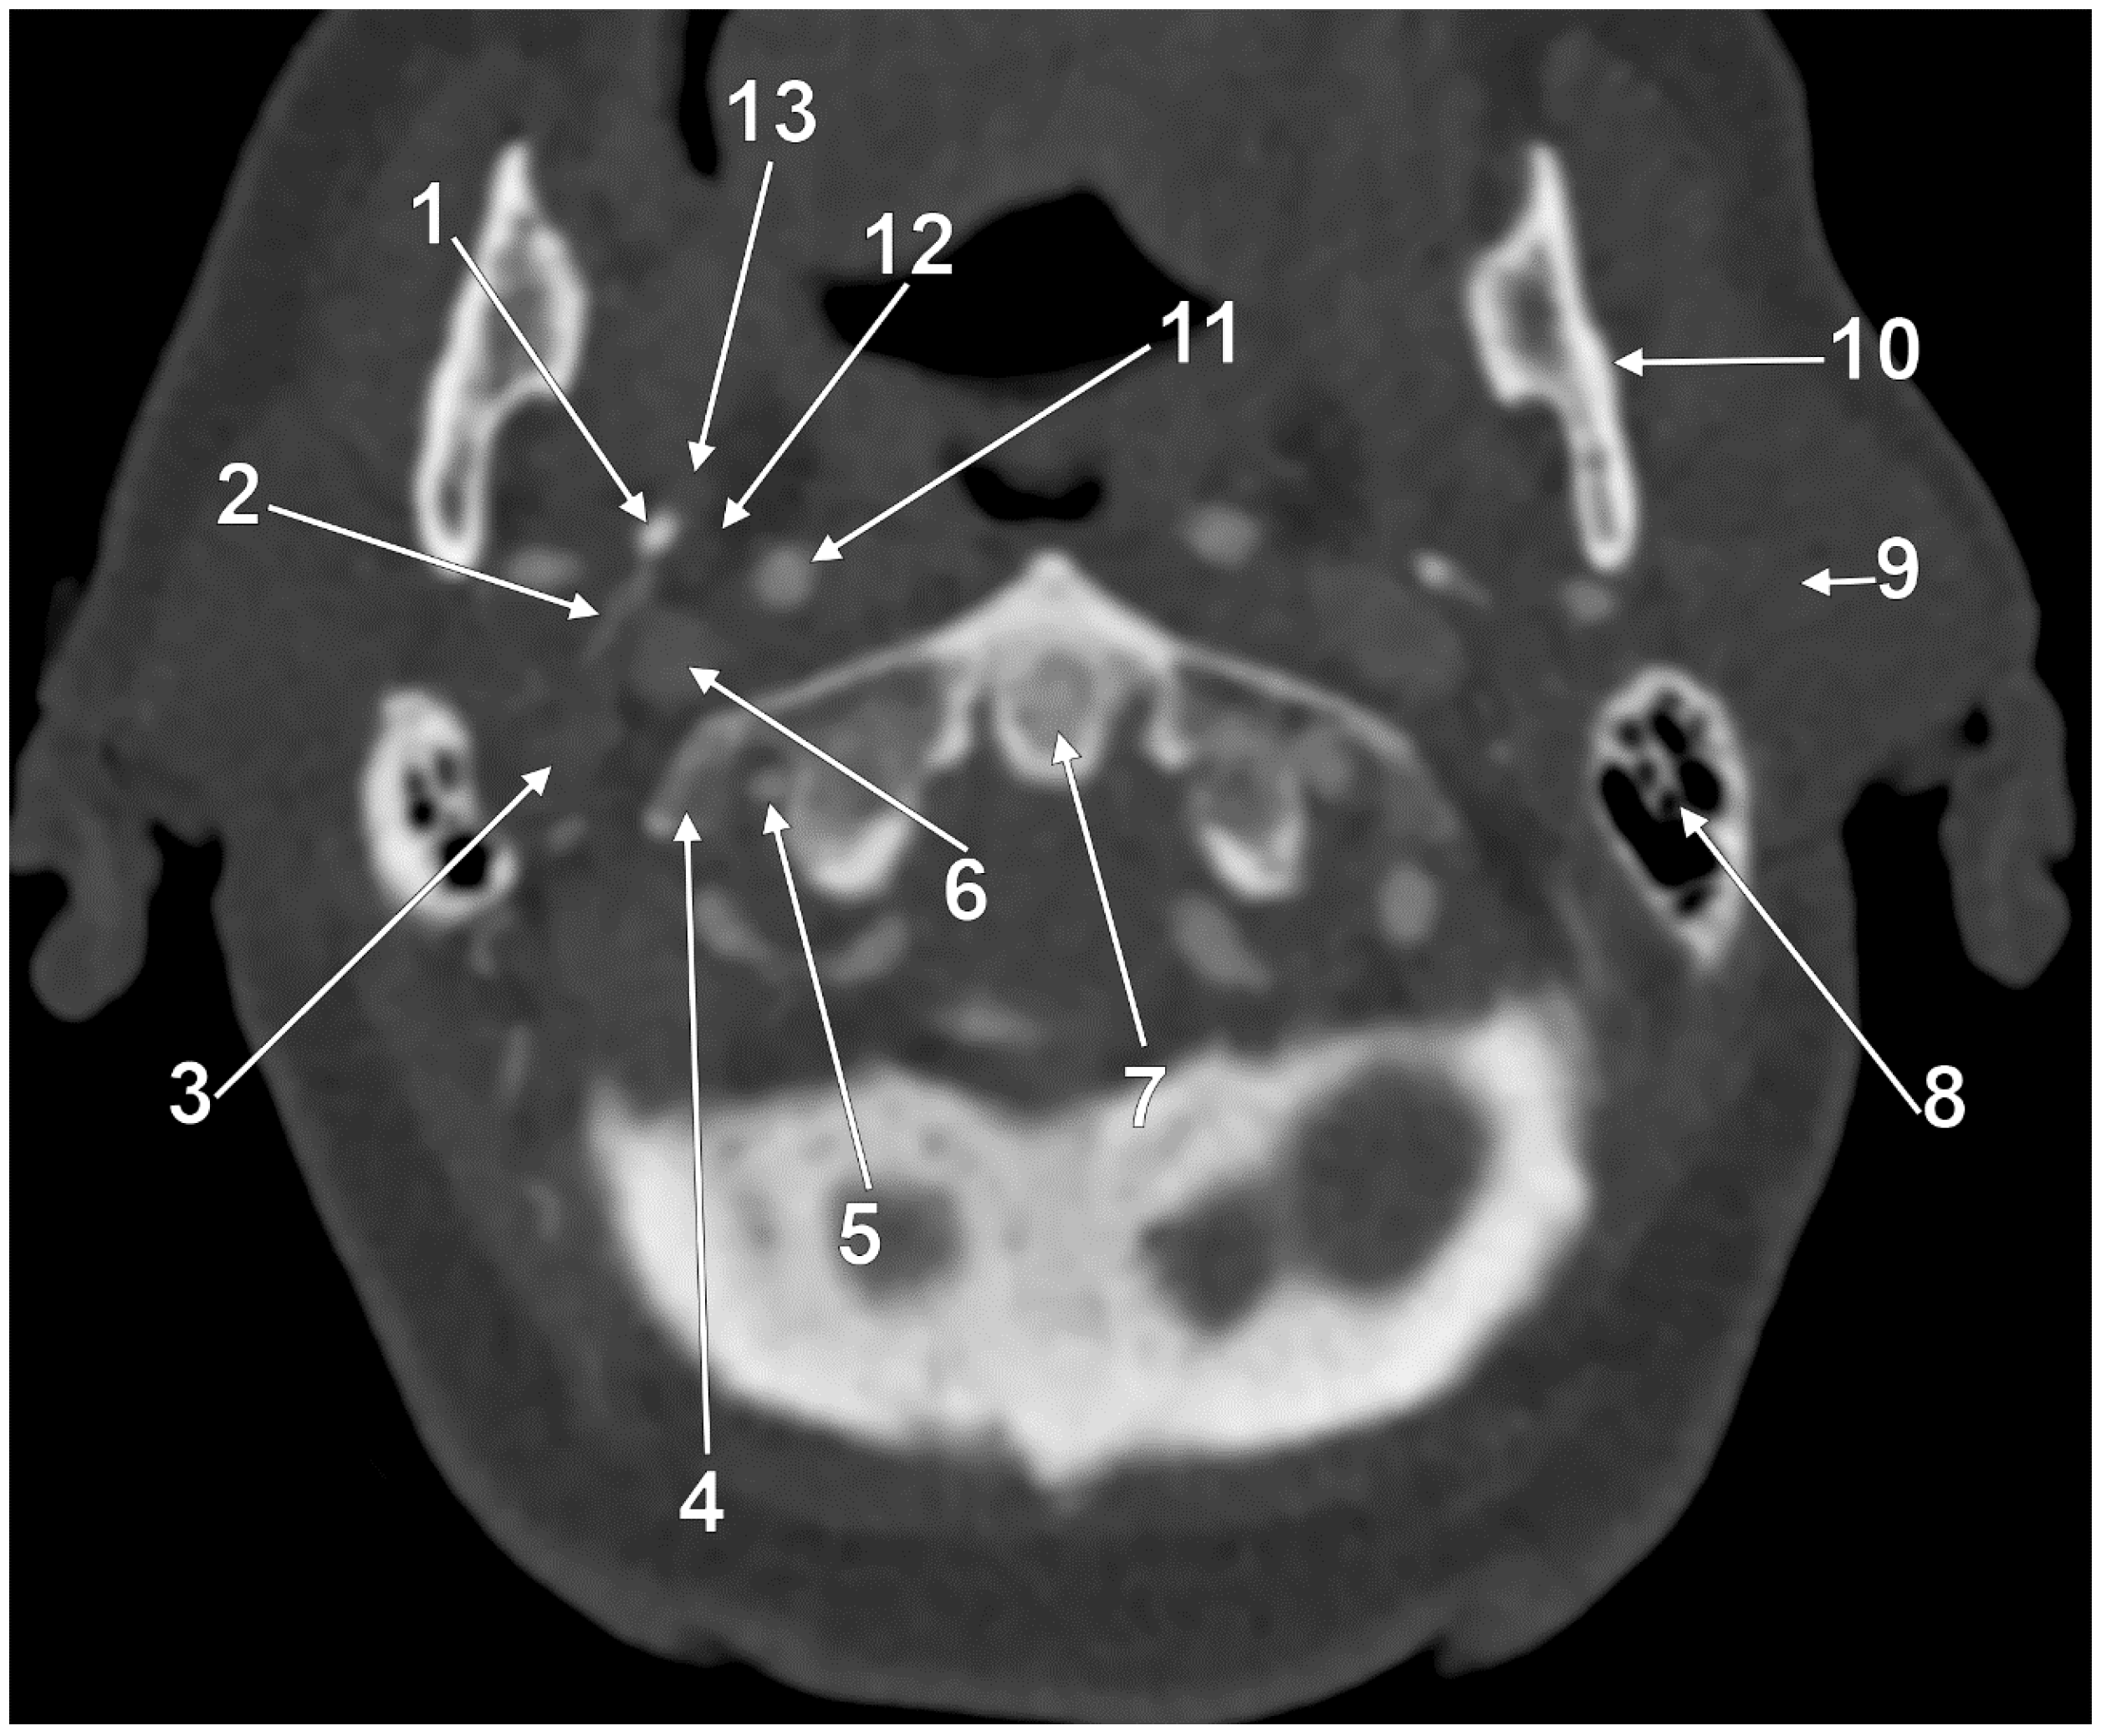

At C1, the IJV descends through a veritable vertical tunnel bordered by different anatomical structures, each of these having the potential to compress the IJV. The tunnel of the IJV is limited: posteriorly, by the C1 transverse process, through which courses the vertebral artery, anteriorly, by the SP, medially, by the ICA, antero-medially, by the stylopharyngeus and styloglossus, laterally, by the posterior belly of the digastric muscle, the SCM, and, eventually, the mastoid process, and anterolaterally, by the deep lobe of the parotid gland and the external carotid artery (ECA) (Figure 1). A retrostyloid course of the ECA [46] will bring it between the SP and the IJV (Figure 2).

At this level, the IJV is usually crossed laterally by the occipital (OA) and posterior auricular (PAA) arteries (Figure 2). The OA may, however, occasionally cross the medial side of the IJV [47]. On the IJV, the deep cervical lymph nodes of the jugular chain are applied, the most representative of these being the subdigastric ganglion or Küttner’s main ganglion [48].